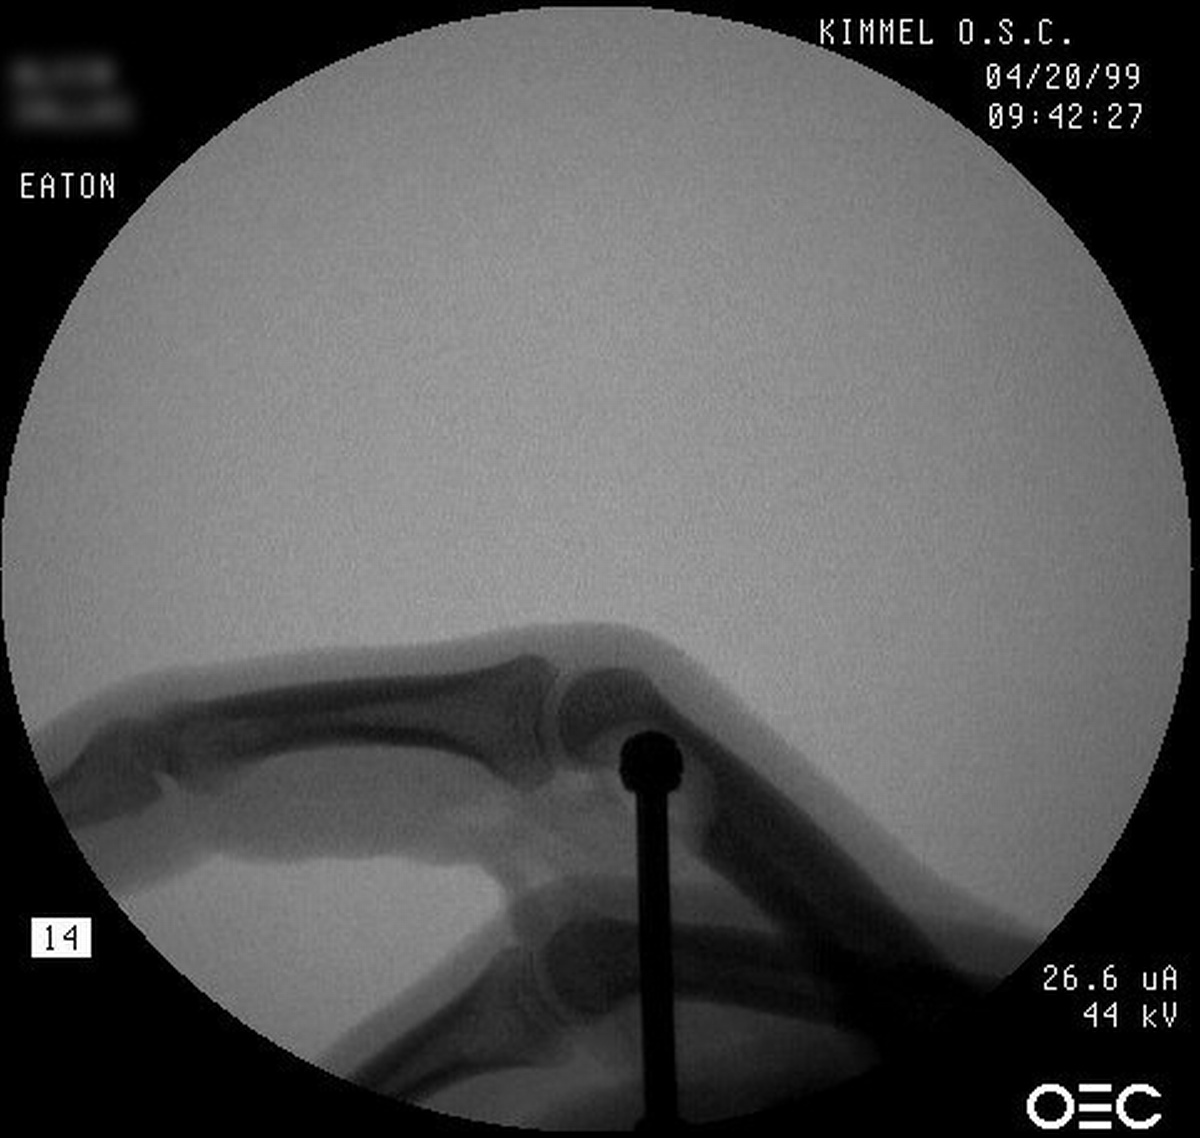

| Case 3. This 26 year old

woman presented with recurrent pain and swelling two years following

excision of an osteoid osteoma of the ring finger middle phalanx head.

Bone scan shows intense activity in this area, consistent with either

persistence or recurrence of osteoid osteoma. |

| The patient was given

perioperative technetium and tumor resection was guided using a

hand held technetium probe. |